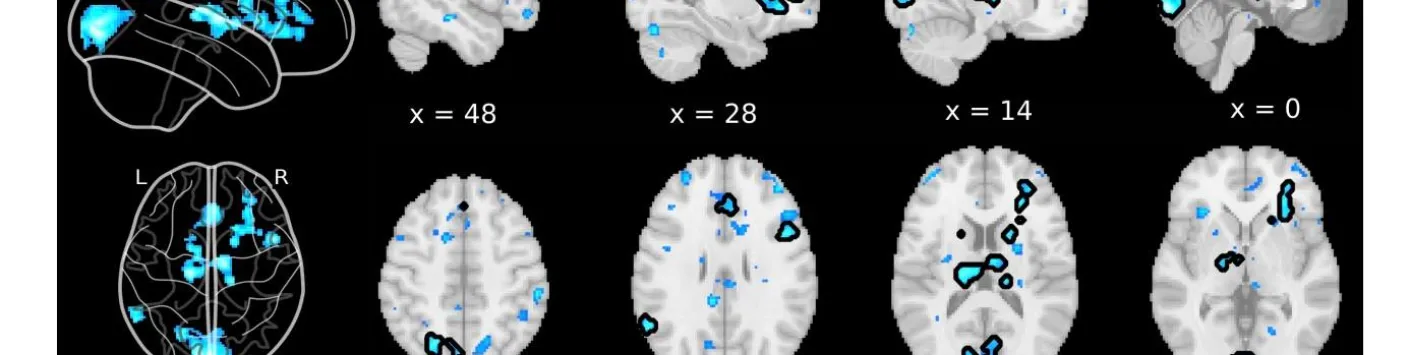

Les désactivations du cerveau entier précèdent les rapports de suppression de l'esprit non induits

➡ Le mind-blanking (MB) est l'expérience de l'incapacité à rapporter des contenus mentaux.

➡ Contrairement à d'autres états mentaux, tels que le vagabondage mental ou les perceptions sensorielles, les corrélats neuronaux de l'aveuglement mental n'ont commencé à être élucidés que récemment.

➡ Il a été démontré que de telles instructions induisent des activations IRMf dans les régions frontales du cerveau, typiquement associées à la métacognition et aux processus d'auto-évaluation, ce qui suggère que la MB pourrait être le résultat d'une suppression intentionnelle du contenu mental.

➡ Ici, les auteurs de cette étude, dont notamment Paradeisios Alexandros Boulakis, Aspirant FNRS Université de Liège, Sepehr Mortaheb Aspirant FNRS Université de Liège, Steve Majerus, Promoteur PDR FNRS Université de Liège et Athena Demertzi, Chercheuse qualifiée FNRS Université de Liège visent à examiner cette hypothèse en déterminant les corrélats neuronaux de la MB sans induction.